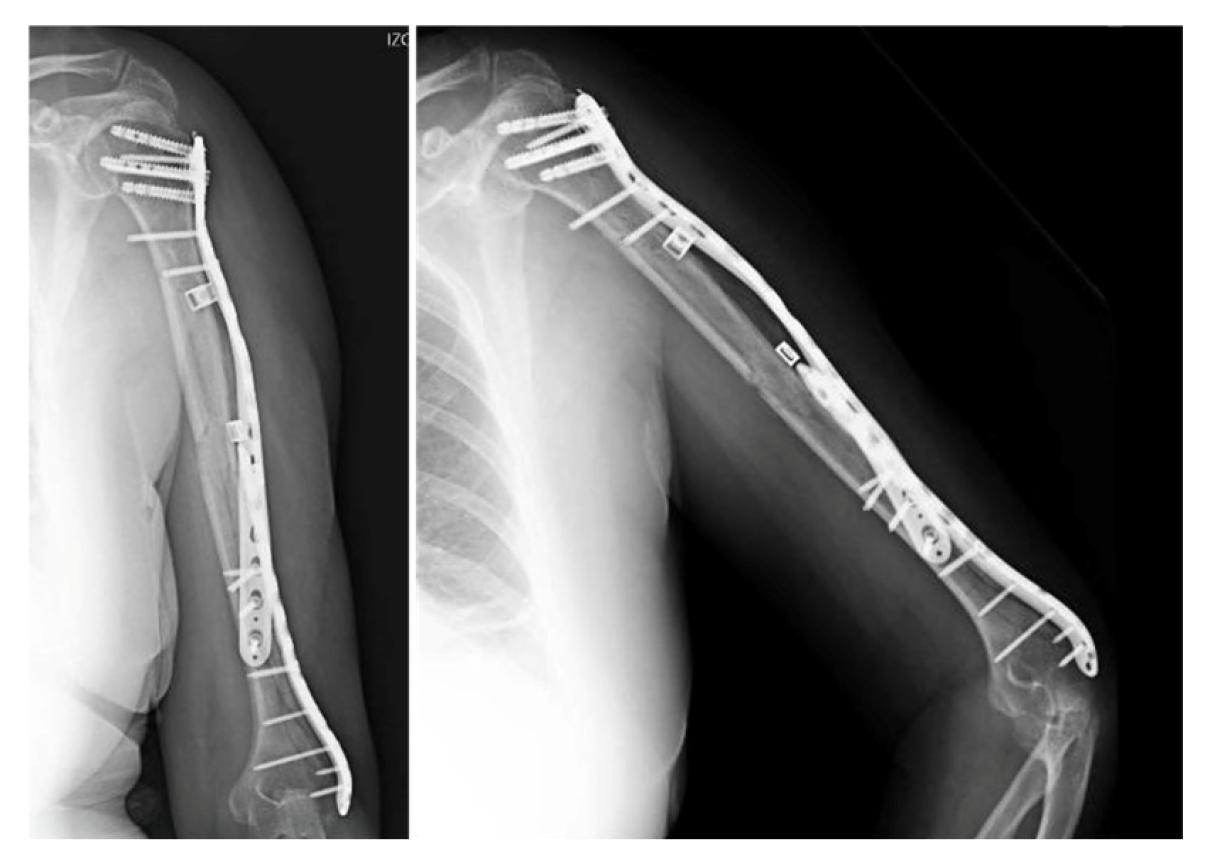

After an initial assessment, a closed reduction was performed followed by placement of an antegrade intramedullary nail. Although there were no issues related to the diameter or curvature of the nail used, a peri-implant fracture occurred at the level of the distal interlocking screw during its insertion, as confirmed by intraoperative fluoroscopy (Figure 2). A decision was made to put an end to the procedure and perform an axial CT-scan to evaluate the morphology of the fracture.

The CT images exhibited a complex fracture originating at the lateral humeral condyle and extending sagittally towards the proximal humerus where it joined the primary spiral fracture, involving the whole of the humeral shaft. Based on this information, it was decided to perform an open reduction and internal fixation of the fracture, using a distal lateral plate combined with a proximal helical plate to ensure a stable fixation.

Figure 2. X-ray and 3D reconstruction of the peri-implant fracture.